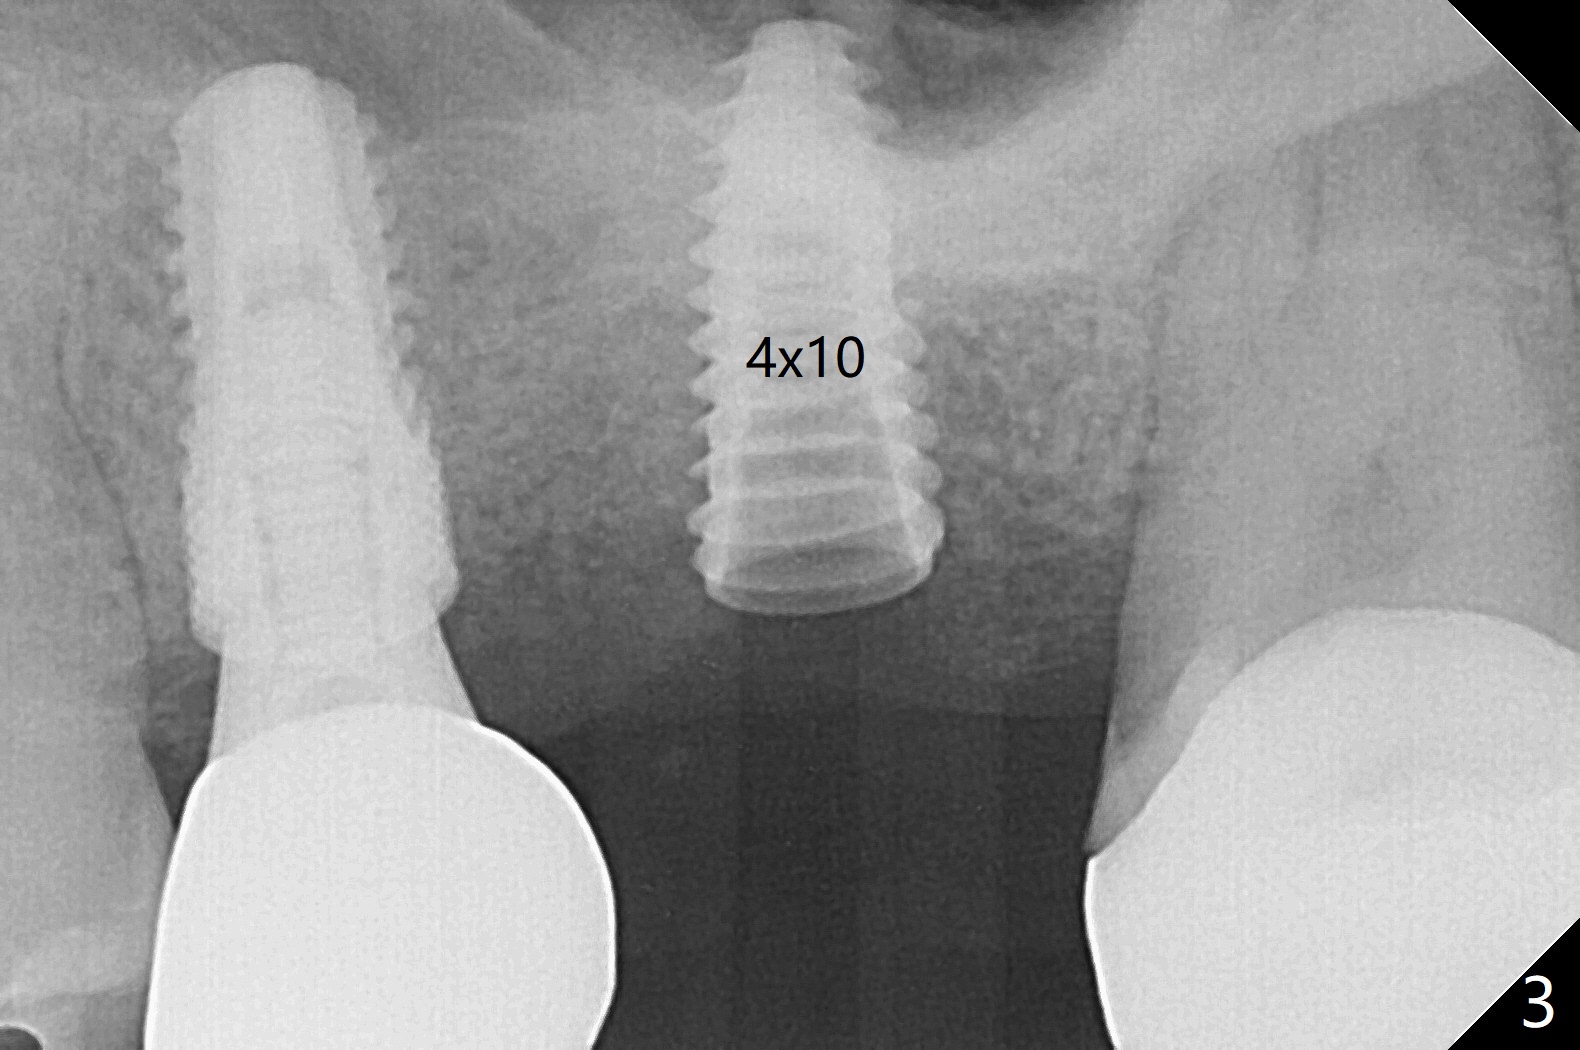

60岁男,左上6(牙根折裂严重骨质吸收)位点保存后6个月,回来植牙。术前CT显示骨质密度低,宽度足够,角化龈也宽,前后牙齿都有牙冠,制作导板麻烦,所以采纳徒手种植。使用4毫米活检打孔刀(Biopsy Punch)进入,简化手术,但是又怕开口不正,不敢用大号植体,术后CT发现钻洞偏颊侧。针对骨质密度低,使用1.2毫米钻头后(约8毫米),使用旋转式骨扩张器直至2.4/3.7毫米(图一(红虚线:原来骨质缺损)逐渐增加深度至11毫米),备洞几乎没有失去骨质,钻洞周围骨质密度谅必增高),取出最后一个扩大器后发现上颌窦底板破裂,放置粘性骨粉,使用4毫米报废植体做上颌窦提升,重复一次(图二,三),稳定性尚可。再次放置骨粉和PRF膜,使用正式植体提升(4.5x8毫米),临床上很难判断是否植体植入牙槽嵴之下(可能骨质疏松),只好拍摄CT(图四,五),好像正好牙槽嵴下,不过又植入骨粉一些(图七:*)。植体扭力~15Ncm,保险起见,放置愈合帽,表面放置少许骨粉以及打孔留下的牙龈(图六:G,之前一直泡在PRF上清液里),牙周胶水固定游离牙龈以及牙周敷料保护。术后6小时没有鼻出血。所以骨质缺损严重,植骨后,虽然缺损外形得到恢复,但是骨头质量,固定植体能力还不够。植牙时,需要适当改变手段,例如使用骨凿,提高骨质密度,而不是单纯使用钻头。术后病人恢复正常,没有疼痛,六天复诊,牙周敷料已经脱落,打孔的牙龈附着颊侧,部分骨粉暴露,但是看样子挺稳定,好像游离牙龈必须缝合。使用树脂敷料牢靠些。术后五周,伤口基本愈合,一处未愈合,与下面骨粉相通,用牙周探针稍微搅动,出血(图九)。擦干血迹,伤口还不错(图十)。术后2个月伤口好像正常愈合(图十一)。术后4.5个月根尖片显示6种植比5深,往后螺纹暴露可能性减少(图十二)。